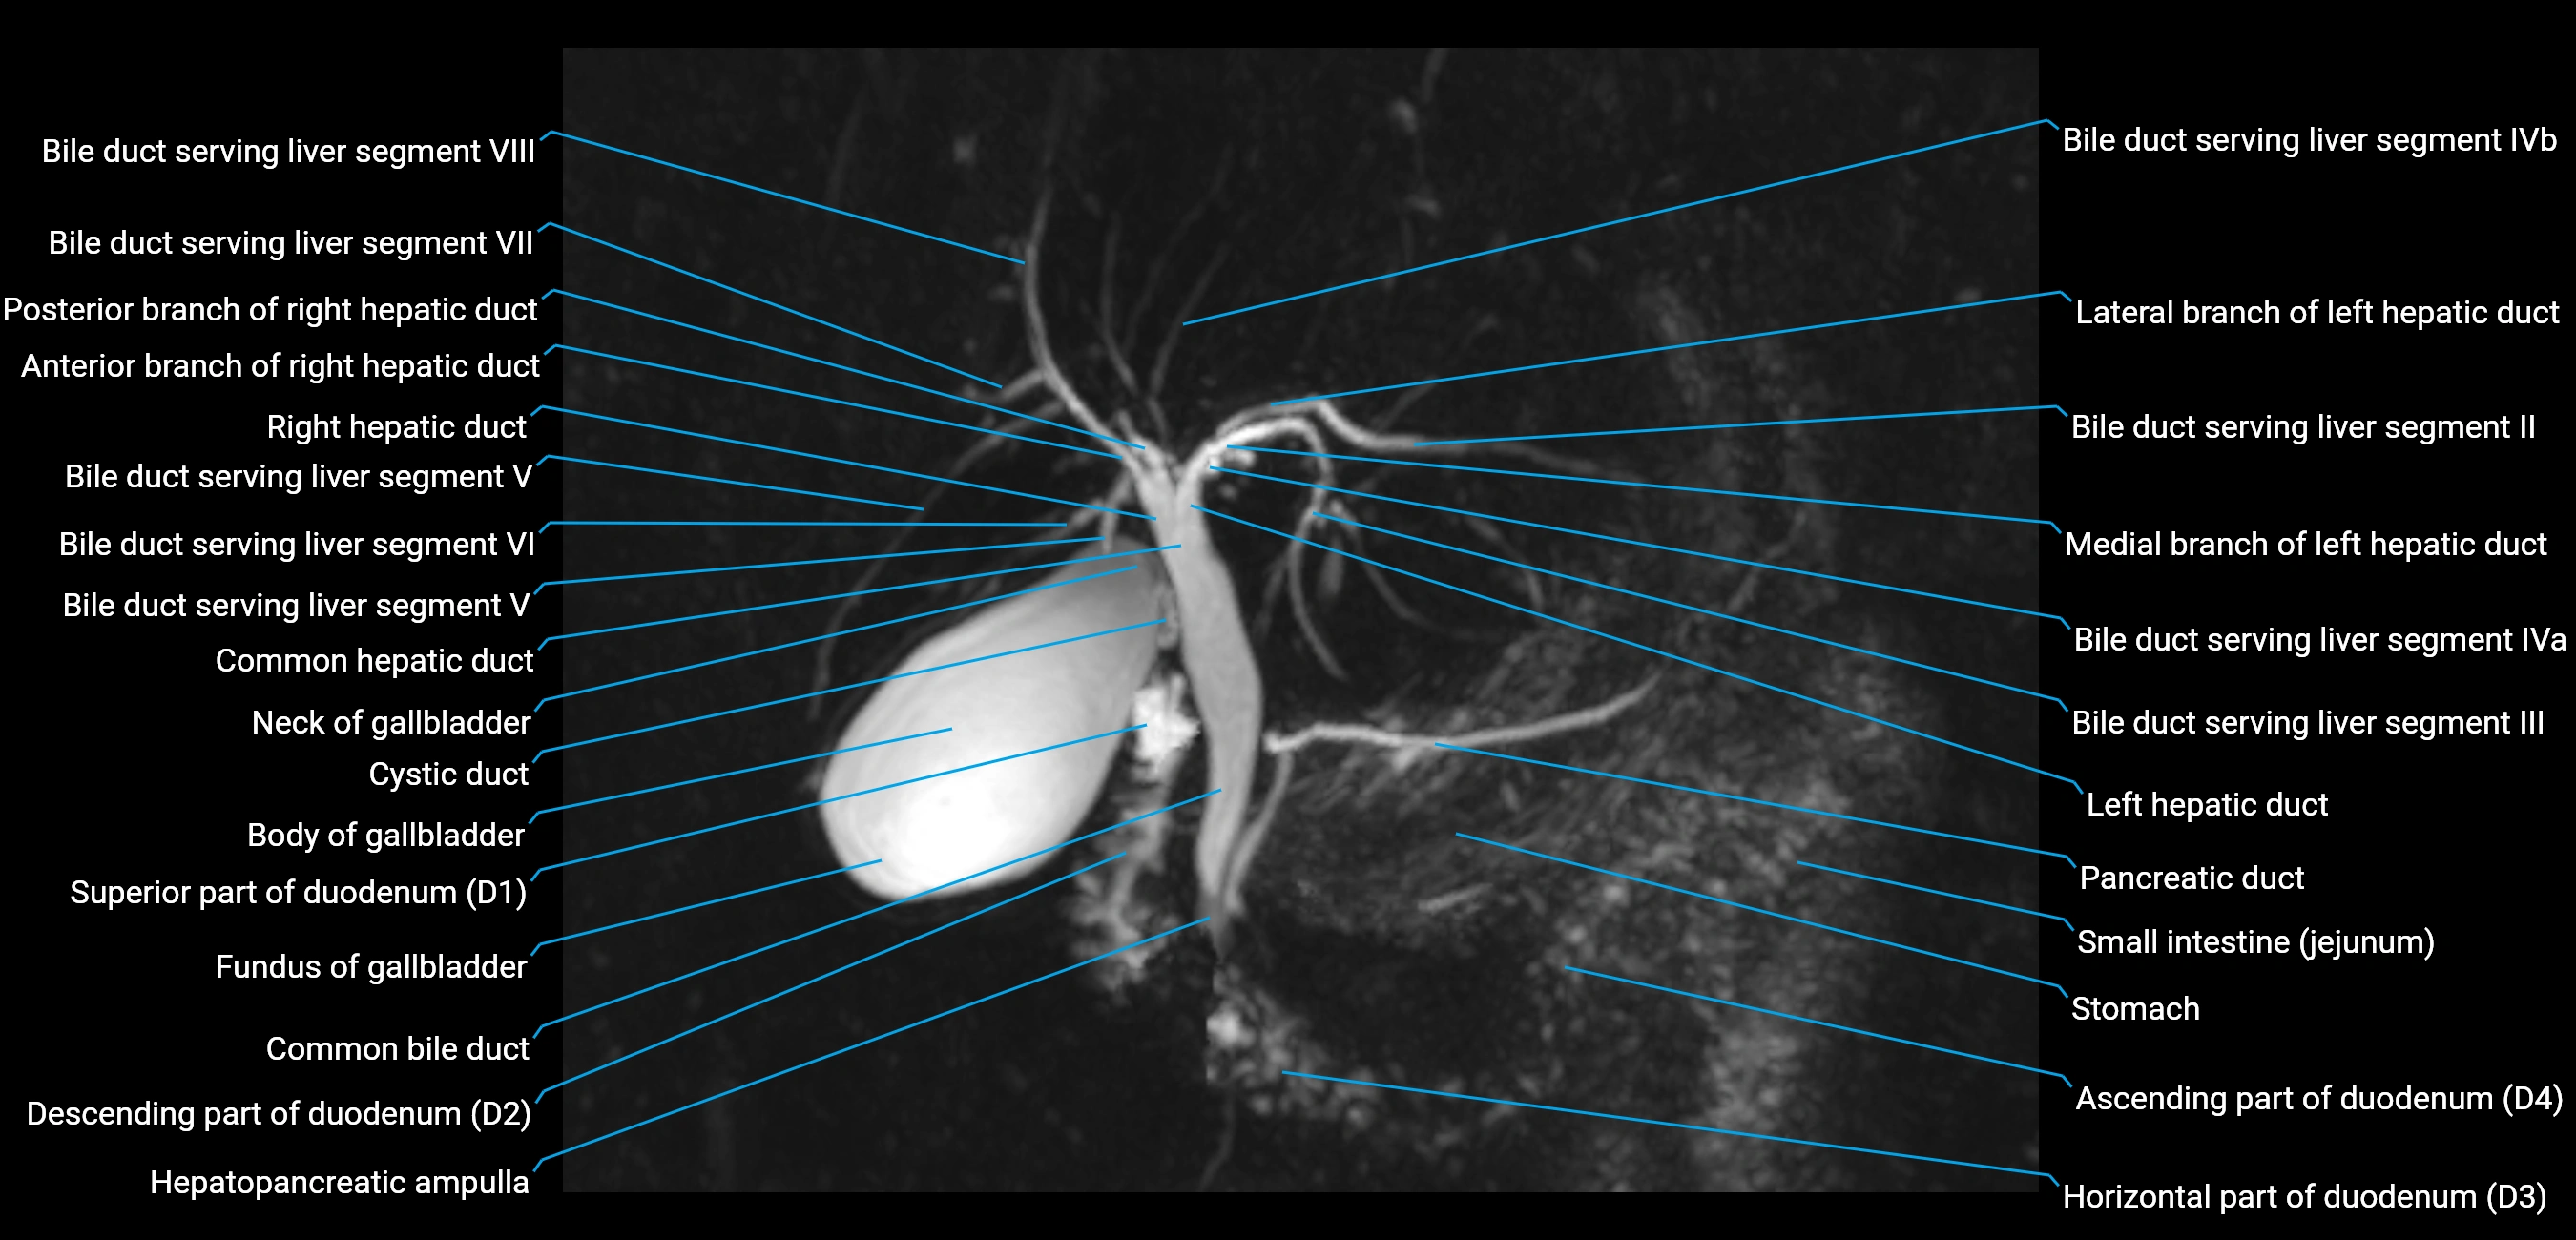

MRI image

image